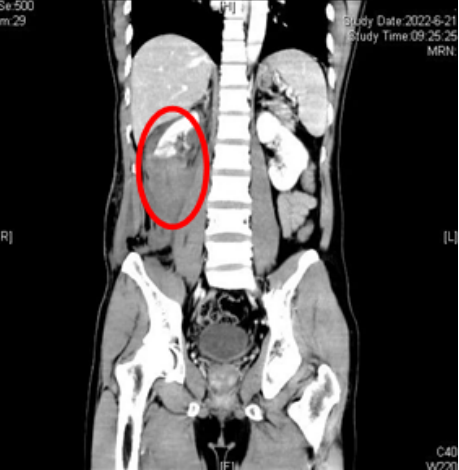

急诊科,入院后医生查体发现张明右侧背部、腰部大面积皮肤擦伤、皮下血肿,急诊CT发现右侧肾脏断裂,腹膜后巨大血肿形成。由于伤势非常严重,立博体育

CT示患者右侧肾脏断裂、肾上极多处皮质裂伤,肾盂破裂,右肾周、腹腔及腹膜后多发积血